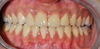

Restauration complète maxillaire et mandibulaire

Eclaircissement et couronnes céramo-céramiques

Restaurations par couronnes céramo-céramiques

Couronnes céramiques sur incisives latérales et facettes sur incisives centrales